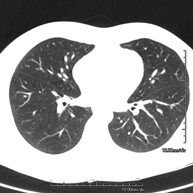

- TC Tòrax

Prova diagnòstica que consisteix en obtenir imatges del tòrax d'alta definició anatòmica (pulmons, cor, mediastí, grans vasos, caixa toràcica, etc. ) mitjançant l'ús d'un equip de TC (Tomografia Computeritzada). Aquestes imatges s'estudien posteriorment en una estació de treball que permet reconstruccions bidimensionals en diferents plànols de l'espai i també reconstruccions 3D (volumètriques). Alguns estudis requereixen l'ús de contrast iodat per millorar la definició de les imatges. - Angio –TC Aorta toràcica

Prova diagnòstica que consisteix en l'estudi de les artèries pulmonars mitjançant l'ús d'un equip de TC (Tomografia Computeritzada) per obtenir imatges bi i tridimensionals. En aquest estudi és imprescindible l'ús de contrast iodat que permet una millor definició anatòmica. Aquesta prova està principalment indicada en els casos de sospita de tromboembòlia pulmonar (TEP) per descartar o confirmar la presència de coàguls sanguinis a l'interior de les artèries. - TC Tòrax d'alta resolució

Prova diagnòstica que consisteix en l'estudi del pulmó mitjançant l'ús d'un equip de TC (Tomografia Computeritzada) per obtenir imatges bi i tridimensional que permeten un estudi anatòmic altament específic del pulmó per poder valorar les estructures anatòmiques de petites dimensions. És una tècnica molt important en l'estudi dels pacients amb sospita de malaltia pulmonar. - TC d'estern